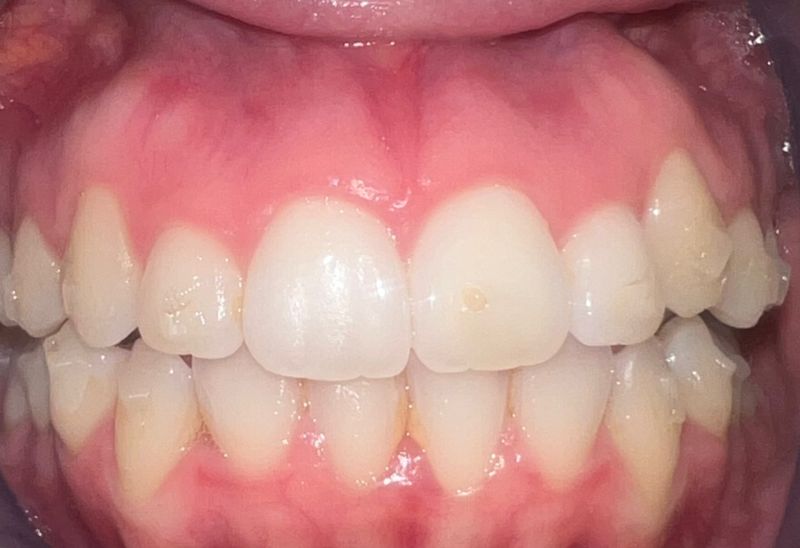

Prima e dopo l'apparecchio invisibile

In questa sezione mostreremo risultati reali ottenuti con l’ortodonzia invisibile a Roma. I cambiamenti riguardano non solo i denti, ma anche l’armonia del viso, la postura orale e l’autostima.